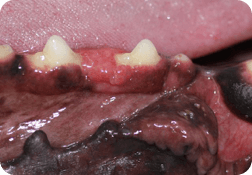

Classifications of the following image growths may be plasma cell tumor, peripheral odontogenic fibroma, focal fibrous hyperplasia, papillary squamous cell carcinoma, lymphoma, pyogenic granuloma, canine acanthomatous ameloblastoma. I’m sure there are a few I’ve missed as well. Take note – the word epulis was not used to describe any of the growths. Epulis is a poor descriptive term. Most previously classified epulides are either peripheral odontogenic fibromas or ossifying fibromas. Also note, that all of the below images look similar and most of them are severe, locally invasive, or symptoms of additional disease.

Many of these tumors require wide margined surgical excision; meaning large parts of the jaw(s) are removed. When taking off parts of the upper jaw, large holes can be made but the lip can cover and make the outcome be quite cosmetic for many cases.

This mass (behind the canine and is subtle) was found very early and had a great outcome. Other larger ones of this type usually do better with adjunctive radiation therapy. Some masses even if found later in the course of disease have great surgical outcomes. For oral tumors it has been shown that all do much better with wide margined surgical excision with or without chemo therapy/radiation as compared to chemo therapy/radiation without surgical excision.